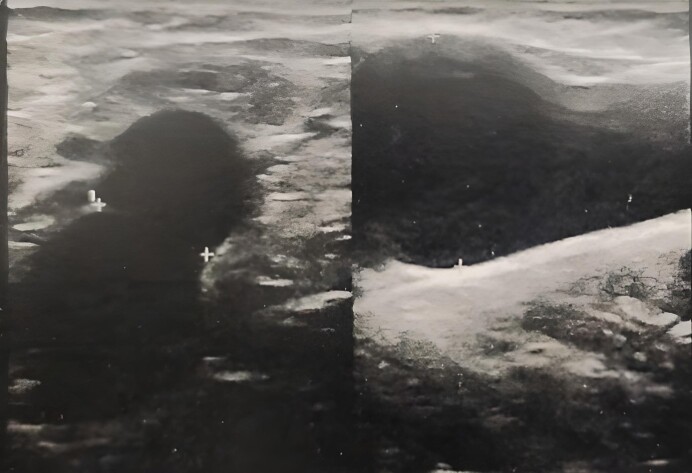

Venous aneurysms are uncommon and can involve the entire venous system and occur at any age. The presence of these aneurysmal formations at the level of the saphenous vein junction is rarely reported, given the small number of cases described in the literature. We report the case of a 41-year-old patient with an aneurysm in the saphenofemoral junction of the right great saphenous vein, discovered incidentally during a consultation for varicose veins of the right lower limb.

Abstract Image